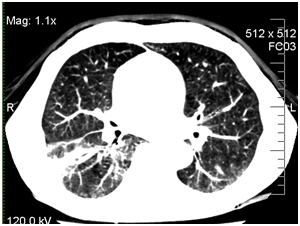

The computed tomography (CT) scans of the chest showed interstitial infiltrates in the right lower lung. Galactomannan test (Platelia Aspergillus, Bio-Rad) in serum was negative. The patient was treated empirically by ceftriaxone 6 g/day and amikacin 1.5g/day. After 3days of continuous high fever, the antibiotic therapy was changed to imepenem 2.0g/day and linezolid 1.2g/day for 10days.

Due to the progression of infection in the right lung, the patient was treated empirically by caspofungin 50mg/day. On day +14 his condition worsened (dyspnea was growing) and he was transferred to ICU. He had persistent pyrexia despite treatment with imepenem, linezolid, and caspofungin. The CT scans of his chest were repeated and revealed a large abscess in the right lower lung. CT of the chest at 14th day revealed interstitial infiltrates with abscess in the right lower lobe (Figure 1).